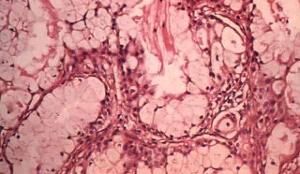

(二)鏡檢:粘液表皮樣癌由粘液樣細胞、表皮樣細胞和中間細胞組成。粘液樣細胞分化成熟時呈杯狀或柱狀,胞漿透明,核在基底部;分化不成熟時,似腺癌細胞,胞漿內含粘液,胭脂紅染色陽性。表皮樣細胞類似口腔黏膜的復層鱗狀上皮,可見細胞間橋,偶見角化。中間細胞呈立方形,體積較小,大小一致,胞漿少,類似上皮的基底細胞。中間細胞可向粘液樣細胞和表皮樣細胞演變。高分化者,粘液樣細胞和表皮樣細胞較多,中間細胞較少,瘤細胞可形成不規則的片狀,但常形成大小不等的囊腔,囊壁襯裡常見粘液細胞。粘液樣細胞可復蓋於表皮樣細胞上,也可夾雜在表皮樣細胞之間。較大的囊腔可有乳頭突入,腔內有紅染的粘液。低分化者,主要為表皮樣細胞和中間細胞,而粘液樣細胞較少,瘤細胞間變明顯,可見核分裂,實質性上皮團塊多,囊腔少,並可見腫瘤向周圍組織侵犯。